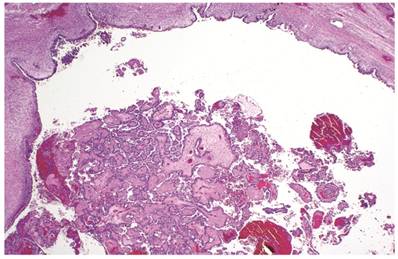

The clinicopathologic features with respect to age, stage, bilaterality, tumor size, gross appearance, and distributions of grade and architectural pattern are shown in Table 4. The histologic appearance was similar to that of the CA components of CA(AF+). Complex intra-cystic growth without destructive invasion of underlying normal ovarian stroma was common (Fig. 5). Twenty-nine tumors (10%) had a mixed carcinoma component of non-clear cell type, 9 of which were associated with endometriosis. A comparison with adenofibromatous clear cell CAs is shown in Table 4.

Figure 5

Clear cell carcinoma arising within an endometriotic cyst. The tumor is entirely intra-cystic.

Associations with endometriosis, including comparison with adenofibromatous clear cell CAs, are shown in Tables 2, 3, and 5. The 57 CAs with endometriosis in the ovarian tumor had the following histologic patterns: tubulocystic (n=4), glandular (n=1), solid (n=4), and papillary (n=8). Mixed patterns occurred in 40. Thirty-one of the 46 (67%) cases arising directly within an endometriotic cyst had a predominantly cystic gross appearance. Foci of epithelial atypia in endometriosis in the ovarian tumor were similar to those in endometriosis associated with APTs noted above (Figs. 6 and 7).